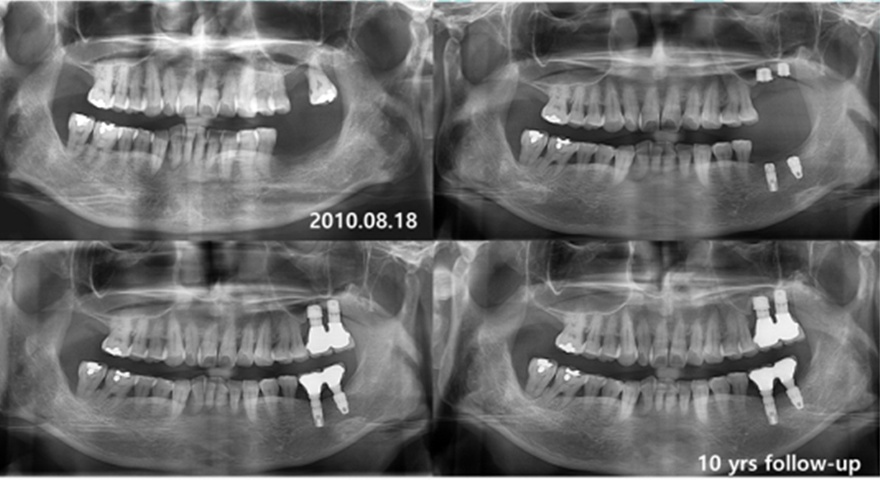

Клінічні випадки:

Одночасне встановлення короткого імплантату INNO

Фото до операції

Передопераційний панорамний знімок

віддалені результати встановлленя короткого імплантату INNO Sub. Short

дані спостережень 8-10 років